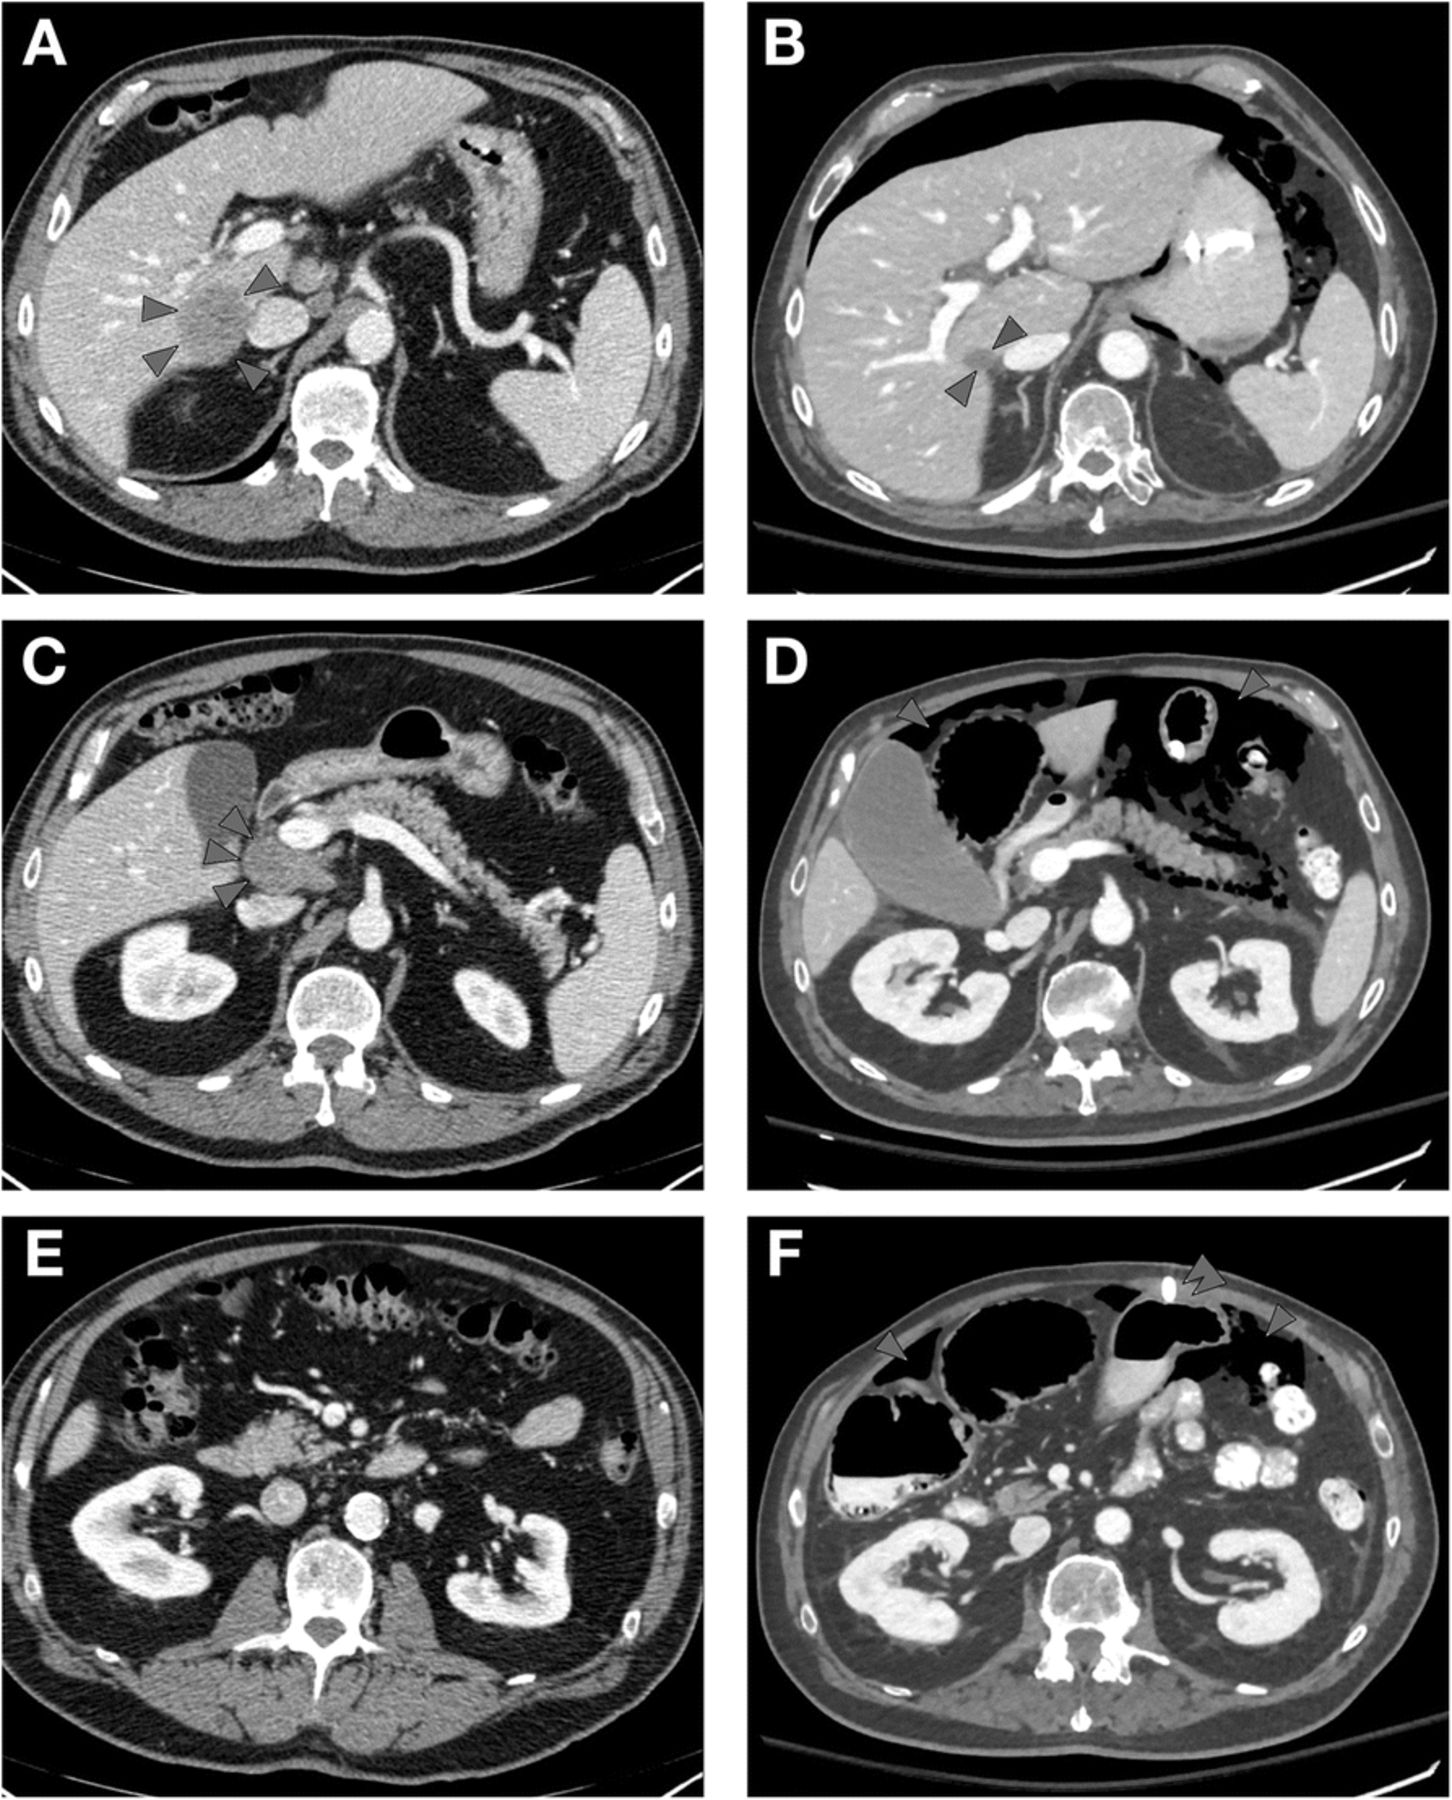

Comparison Of Mdct Mri And Mri With Diffusion Weighted Imaging In

Pdf Comparison Of Mdct Mri And Mri With Diffusion Weighted

Multi Modality Imaging Features Distinguish Pancreatic Carcinoma

Multi Modality Imaging Features Distinguish Pancreatic Carcinoma

Multi Modality Imaging Features Distinguish Pancreatic Carcinoma